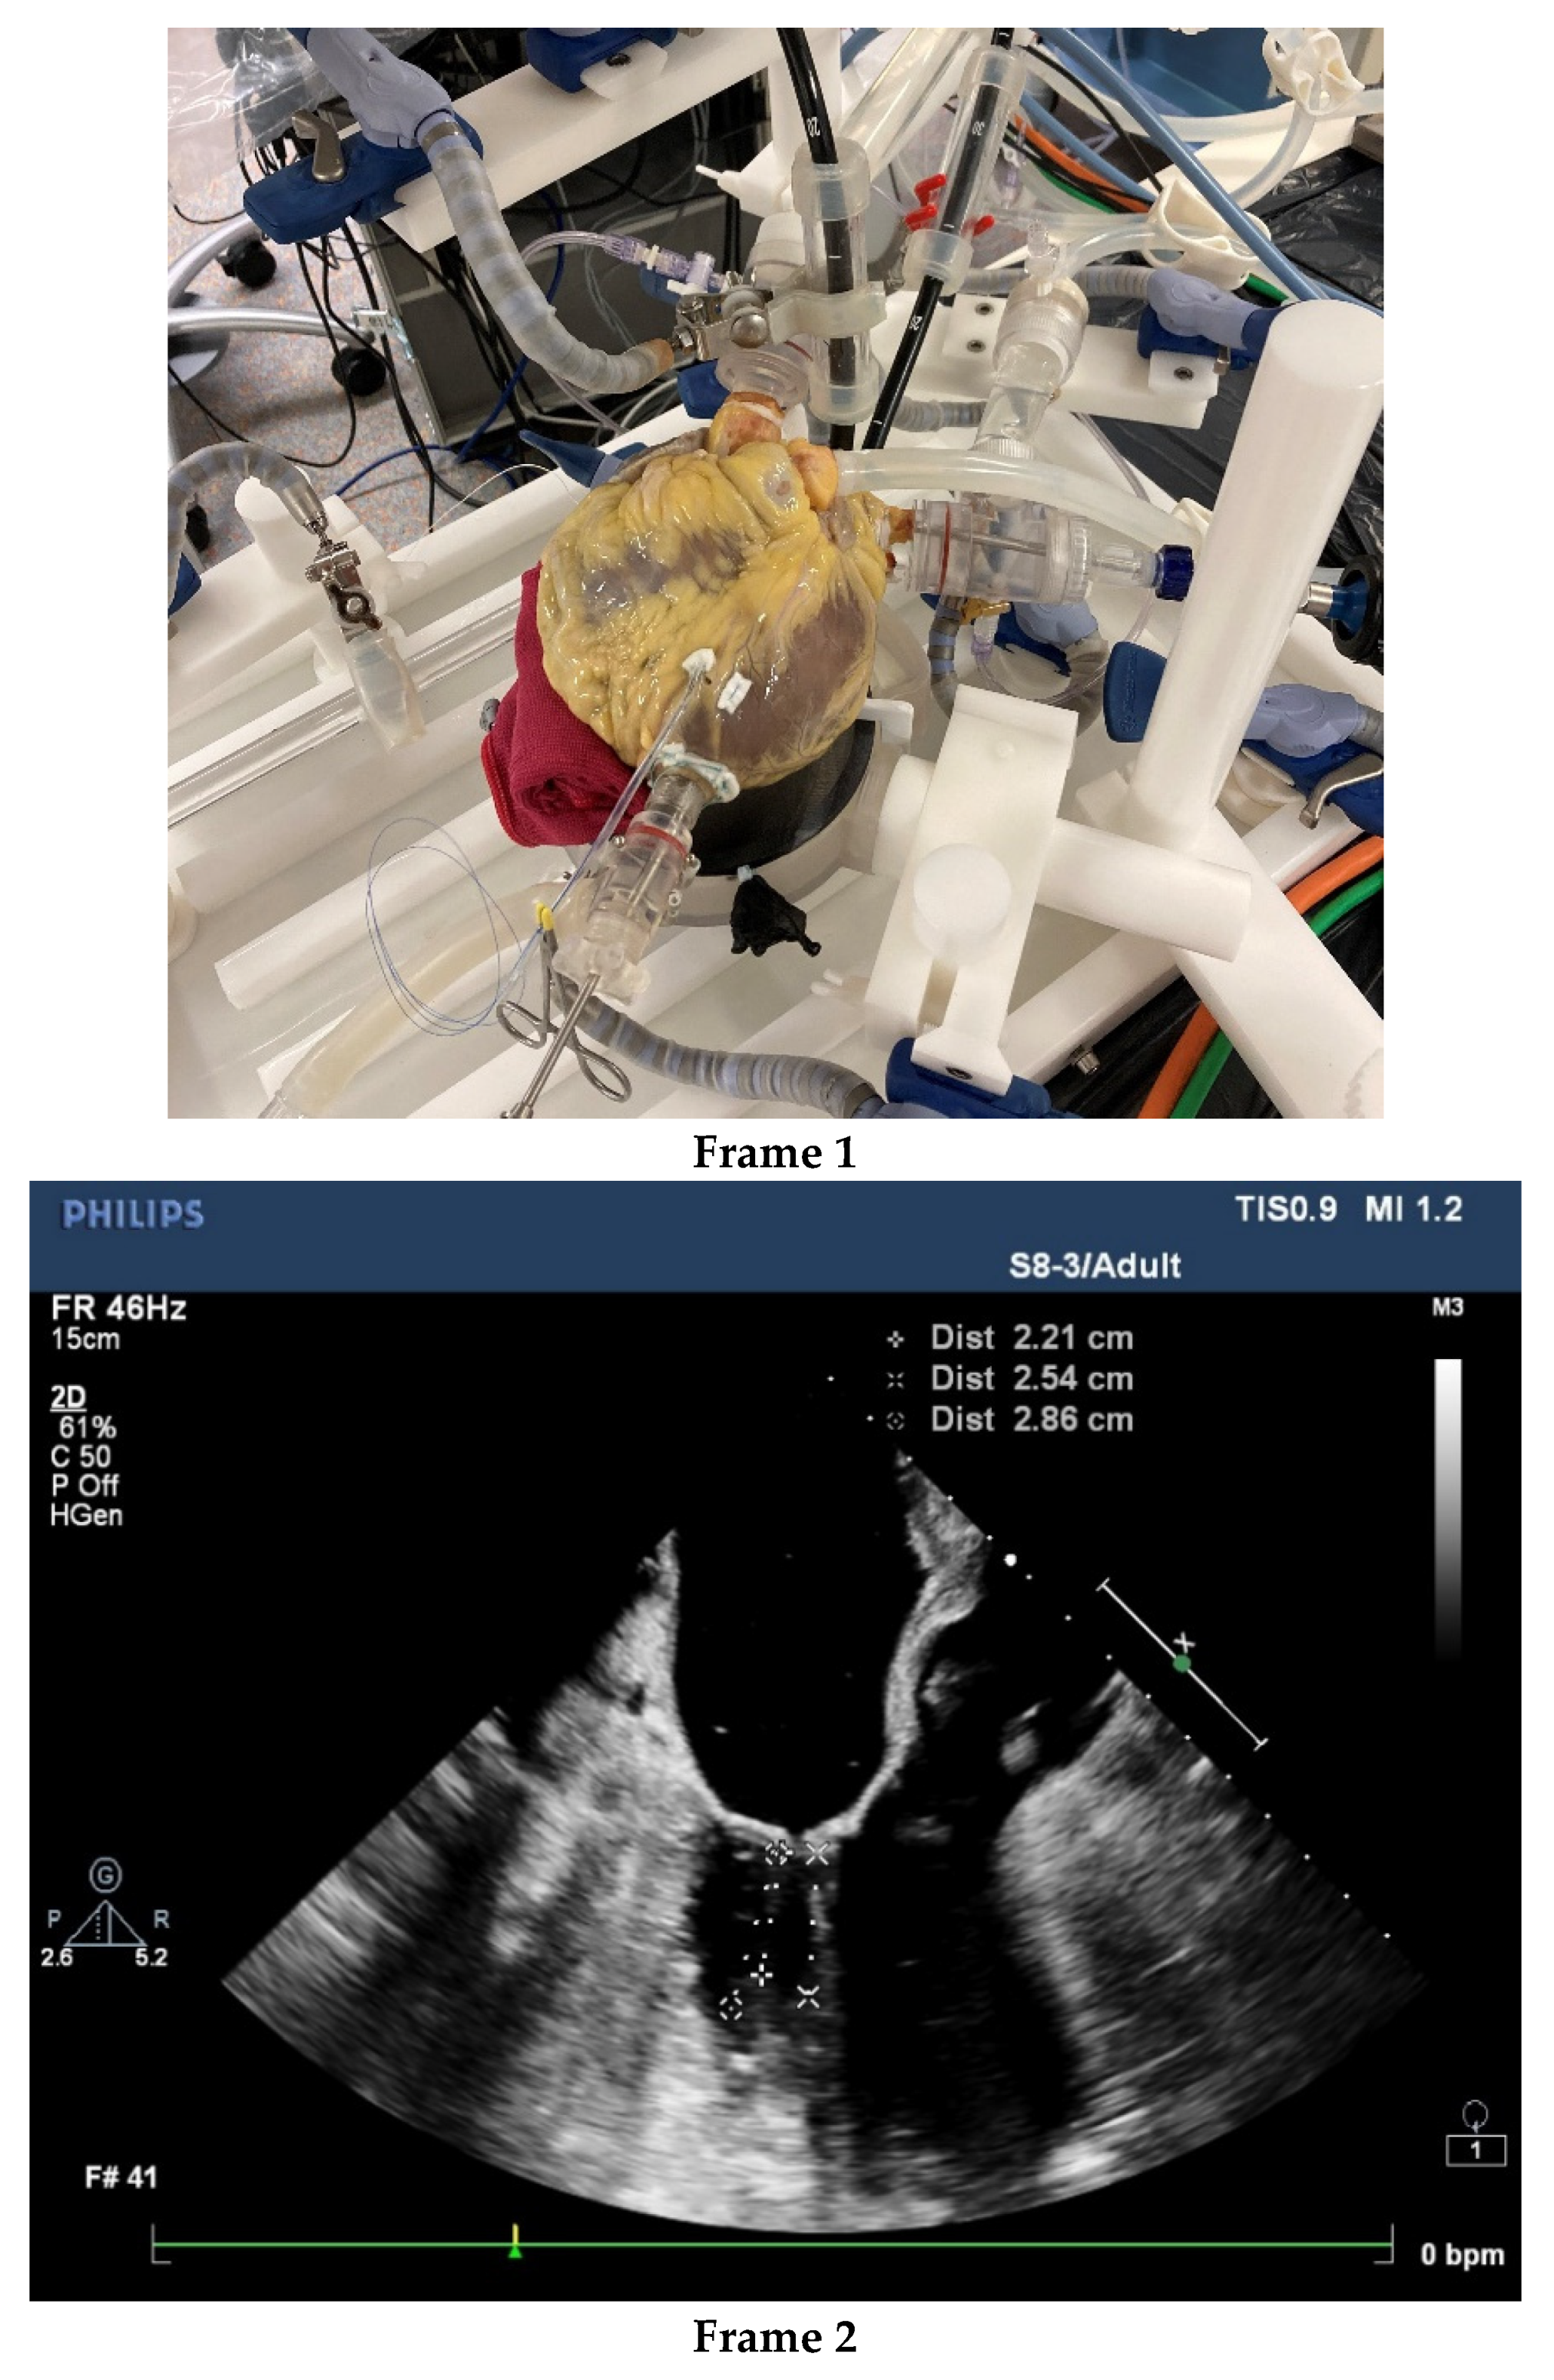

The aforementioned imaging add-ons may simplify surgical duties and tasks despite their technical complexity, but these require specialized knowledge and computer competence. Computer/ robotic assistance also forces surgeons to reflect on the boundaries of their surgical proficiency and skill building. Control of the surgical surroundings has become far more complex than the operation itself. The proficiency of the surgical team and the institution should be critically examined. From admission to rehabilitation care, within a surgical group and the institution, minimal invasiveness must be the common interventional approach supported by adequate infrastructure, cost-effective logistics and educated and skilled workers. Surgeons are not infallible and, in our experience, some cases of bleeding and death were associated with suboptimal surgical performance. It remains a challenge to select surgeons for MIMVS and to train them effectively. Apart from learning-by-doing, simulators may be used to select candidates for MIMVS and accelerate proficiency, especially if human cadaver hearts are used [75,76,77]. See Figure 2.

Figure 2.

After thawing, the human cadaver heart is embalmed with a specialized solution of a very low toxicity. This embalmment ensures preservation, safe and user-friendly handling of the heart and tools and improves tissue quality, which allows for physiologic load of the heart, although protection measures always remain in place. Frame 1. provides an external view of the embalmed human cadaver heart. Frame 2. shows a TEE of the pulsating heart with an assessment of the diameter of the mitral valve diameter, the association with the aortic valve and length of chordae. Frame 3. presents a still of the videoscopic presentation of the left ventricle and partial left atrium.

Beating human cadaver hearts with intact arterial and venous connections provide an excellent real-life training platform. In prescreening, the human cadaver heart can be inspected and tested, to ensure that the heart is suitable for the test or teaching requirements. Such a platform can be placed in a cath-lab imaging environment including 3-D echocardiography. The setting is not only effective for testing devices, but also for assessing how much imaging information and device handling a trained operator can safely master. The platform may reveal complex usability issues relevant to organizing the work processes and safe learning of MIMVS by junior surgeons and to mastering new technology by advanced surgeons. Safe and fast MIMVS starts with excellent surgeons, and in our opinion technical innovation is no substitute for suboptimal surgical skills. In contrast, high-tech support for moderately competent surgeons may create serious additional risks, including the interruption of workflow [78].